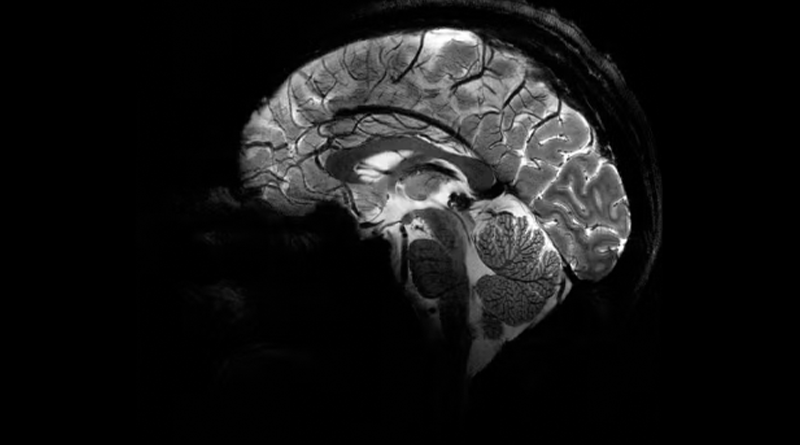

Imagem do Iseult com um campo magnético de 11,7 teslas. — Foto: Reprodução/Comissão de Energia Atômica da França (CEA)

A Comissão de Energia Atômica da França (CEA) divulgou nesta terça-feira (2) as primeiras imagens do cérebro humano feitas pelo aparelho de ressonância magnética mais potente do mundo. De acordo com os responsáveis pelo projeto, o scanner atingiu um nível de precisão jamais visto, algo que pode ser decisivo para detectar doenças.

O campo magnético criado pelo scanner é de 11,7 teslas. Essa potência permite que a máquina escaneie imagens 10 vezes mais precisas do que os aparelhos normalmente utilizados em hospitais – cuja potência geralmente não supera os três teslas.

Em uma tela de computador, Vignaud comparou imagens tiradas por esse poderoso scanner, apelidado de Iseult, com imagens de uma ressonância magnética normal.

“Com essa máquina podemos ver os pequenos vasos que alimentam o córtex cerebral, ou detalhes do cérebro que eram quase invisíveis até agora”, detalha.